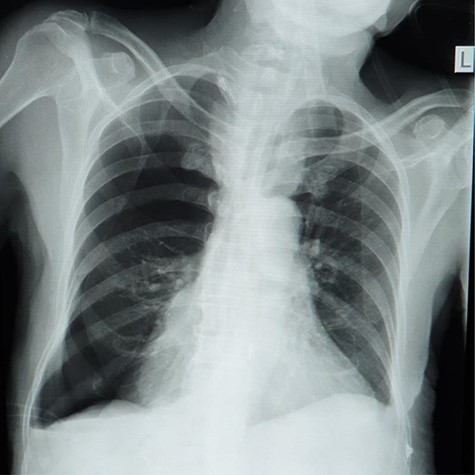

The report revealed a segment of colon with low-grade invasive adenocarcinoma (pT3NxM1) and Schistosoma eggs embedded in the tumor (Fig. 3).

(A) Histopathology of colon with adenocarcinoma associated with Schistosoma ova with poorly formed granulomatous inflammation, hematoxylin and eosin (H&E) ×20 magnification. (B) Adenocarcinoma and Schistosoma ova with dense lymphocytic infiltrates ×40 magnification.